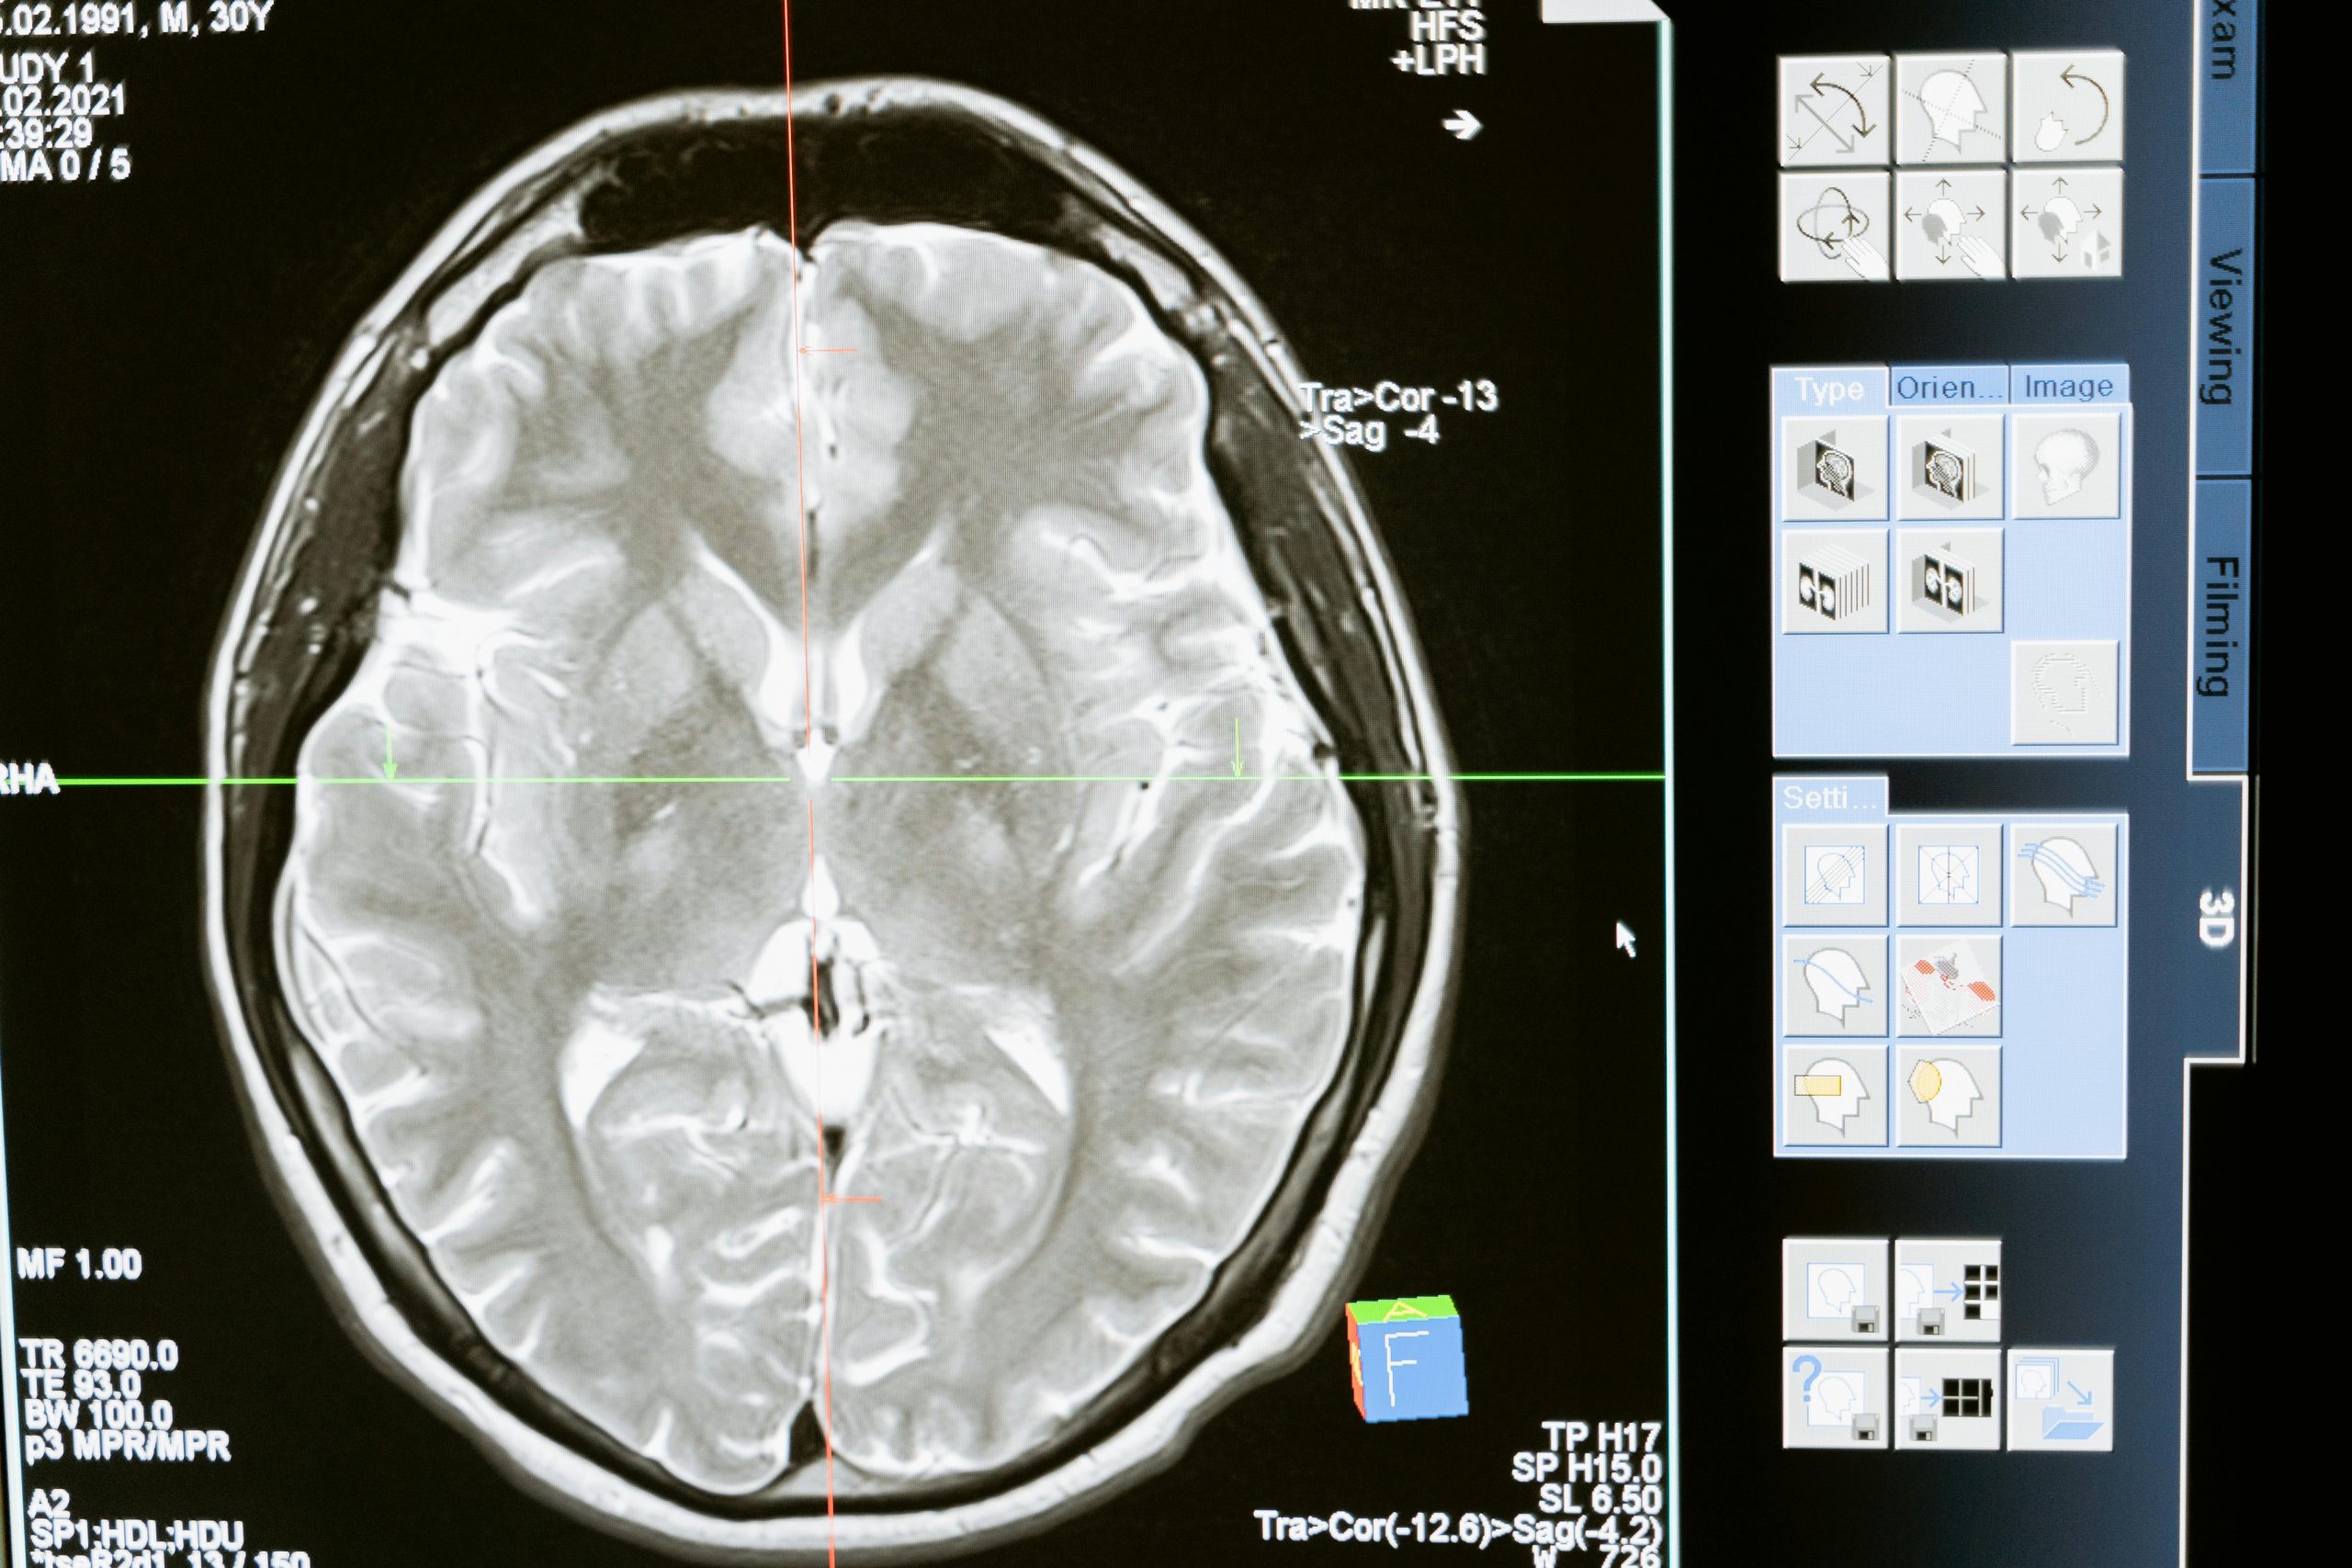

At Michiana Neurologic Medicine, we provide comprehensive care for a wide range of neurological conditions, from migraine treatment and multiple sclerosis (MS) care to generalized myasthenia gravis (gMG) and neuromyelitis optica spectrum disorder (NMOSD). Our expert team of neurologists offers advanced diagnostic testing, including EMG and EEG, and cutting-edge treatments such as infusion therapies, BOTOX® for migraines, and occipital nerve blocks.

Michiana Neurologic Medicine offers onsite testing to diagnose many neurological illnesses, including EEG’s, EMG’s, cognitive screening, and more. All testing is conducted at our clinic.